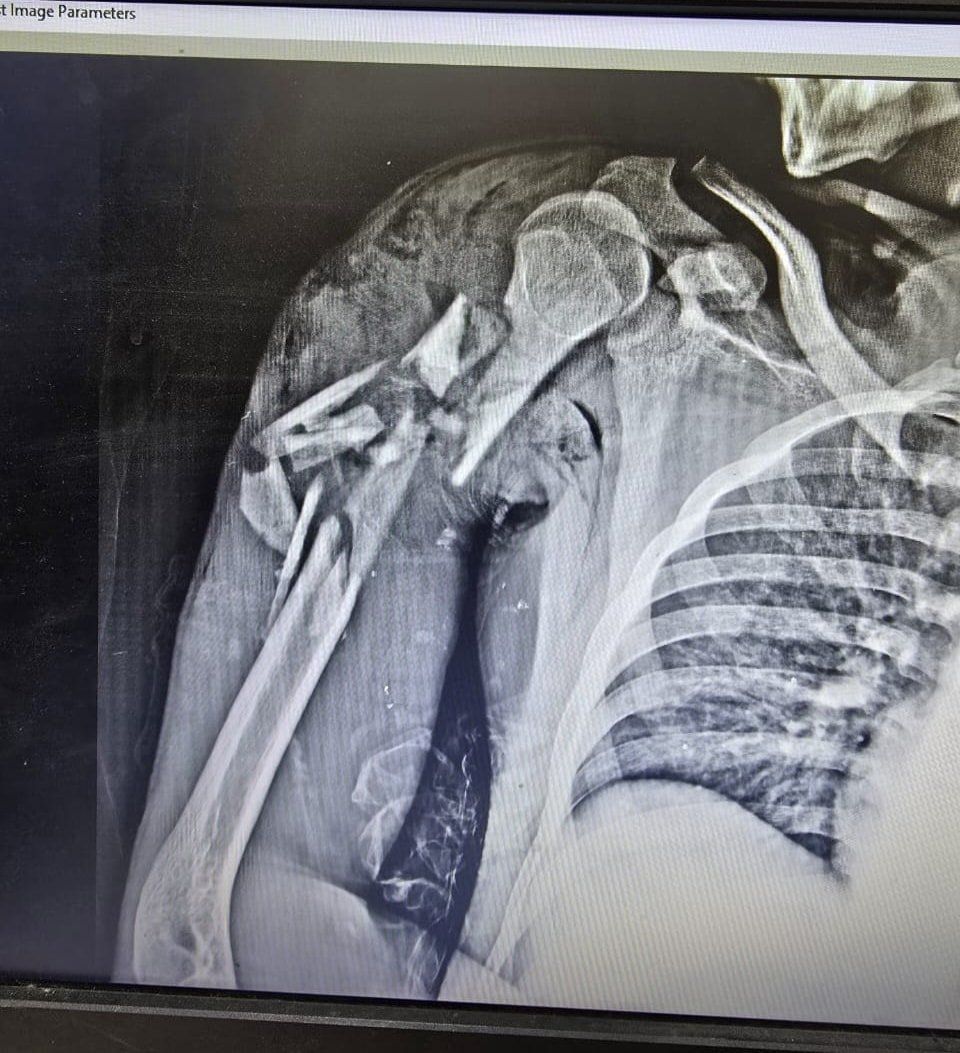

الإثنين، 06 أكتوبر 2025 01:50 منجح فريق جراحي بمستشفى قها التخصصي، التابعة لأمانة المستشفيات المتخصصة بوزارة الصحة، بمحافظة القليوبية، في إنقاذ حياة شاب في الـ20 من عمره، اصطدم به قطار، وكاد الحادث أن يودي بحياته، وتسبب في إصابته بكسر متفتت مفتوح مع فقد جزء من العظام بالعضد الأيمن مع قطع بالعضلات، وكسر متفتت مفتوح مع فقد جزء من العظام بالساق الأيمن مع قطع بالعضلات، وتهتك بالقدم اليمنى وقطع بالأوتار والعضلات، مع كسر بعظام القدم.

وتابعت المستشفى، أنه تم تجهيز المريض ولياقته من قسم التخدير وتحضيره وتجهيز الدم والبلازما اللازمة للحالة، حيث استقر التشخيص علي كسر متفتت مفتوح مع فقد جزء من العظام بالعضد الأيمن مع قطع بالعضلات، وكسر متفتت مفتوح مع فقد جزء من العظام بالساق الأيمن مع قطع بالعضلات، وتهتك بالقدم اليمنى وقطع بالأوتار والعضلات، مع كسر بعظام القدم.

كسور بجسم الشاب بعد الحادث

الأشعة الخاصة بالمريض